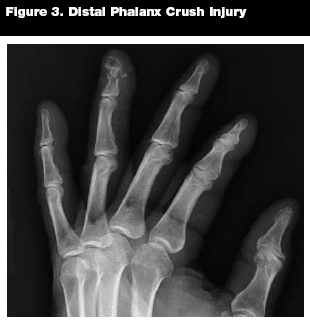

Epidemiology. Phalanx fractures are commonly seen in the ED. Distal phalanx fractures are the most common fractures of the hand, accounting for more than half of hand fractures.13,14 (See Figure 3.) Proximal and middle phalanx fractures are also common, and may be viewed as similar injuries by the emergency physician.13

Patterns of Injury. Distal phalanx fractures often result from crush injuries and may be associated with soft-tissue injuries and/or nailbed lacerations.14,15 Proximal and middle phalanx injuries are often associated with sports such as basketball, but can result from any angular force to the finger.14,16